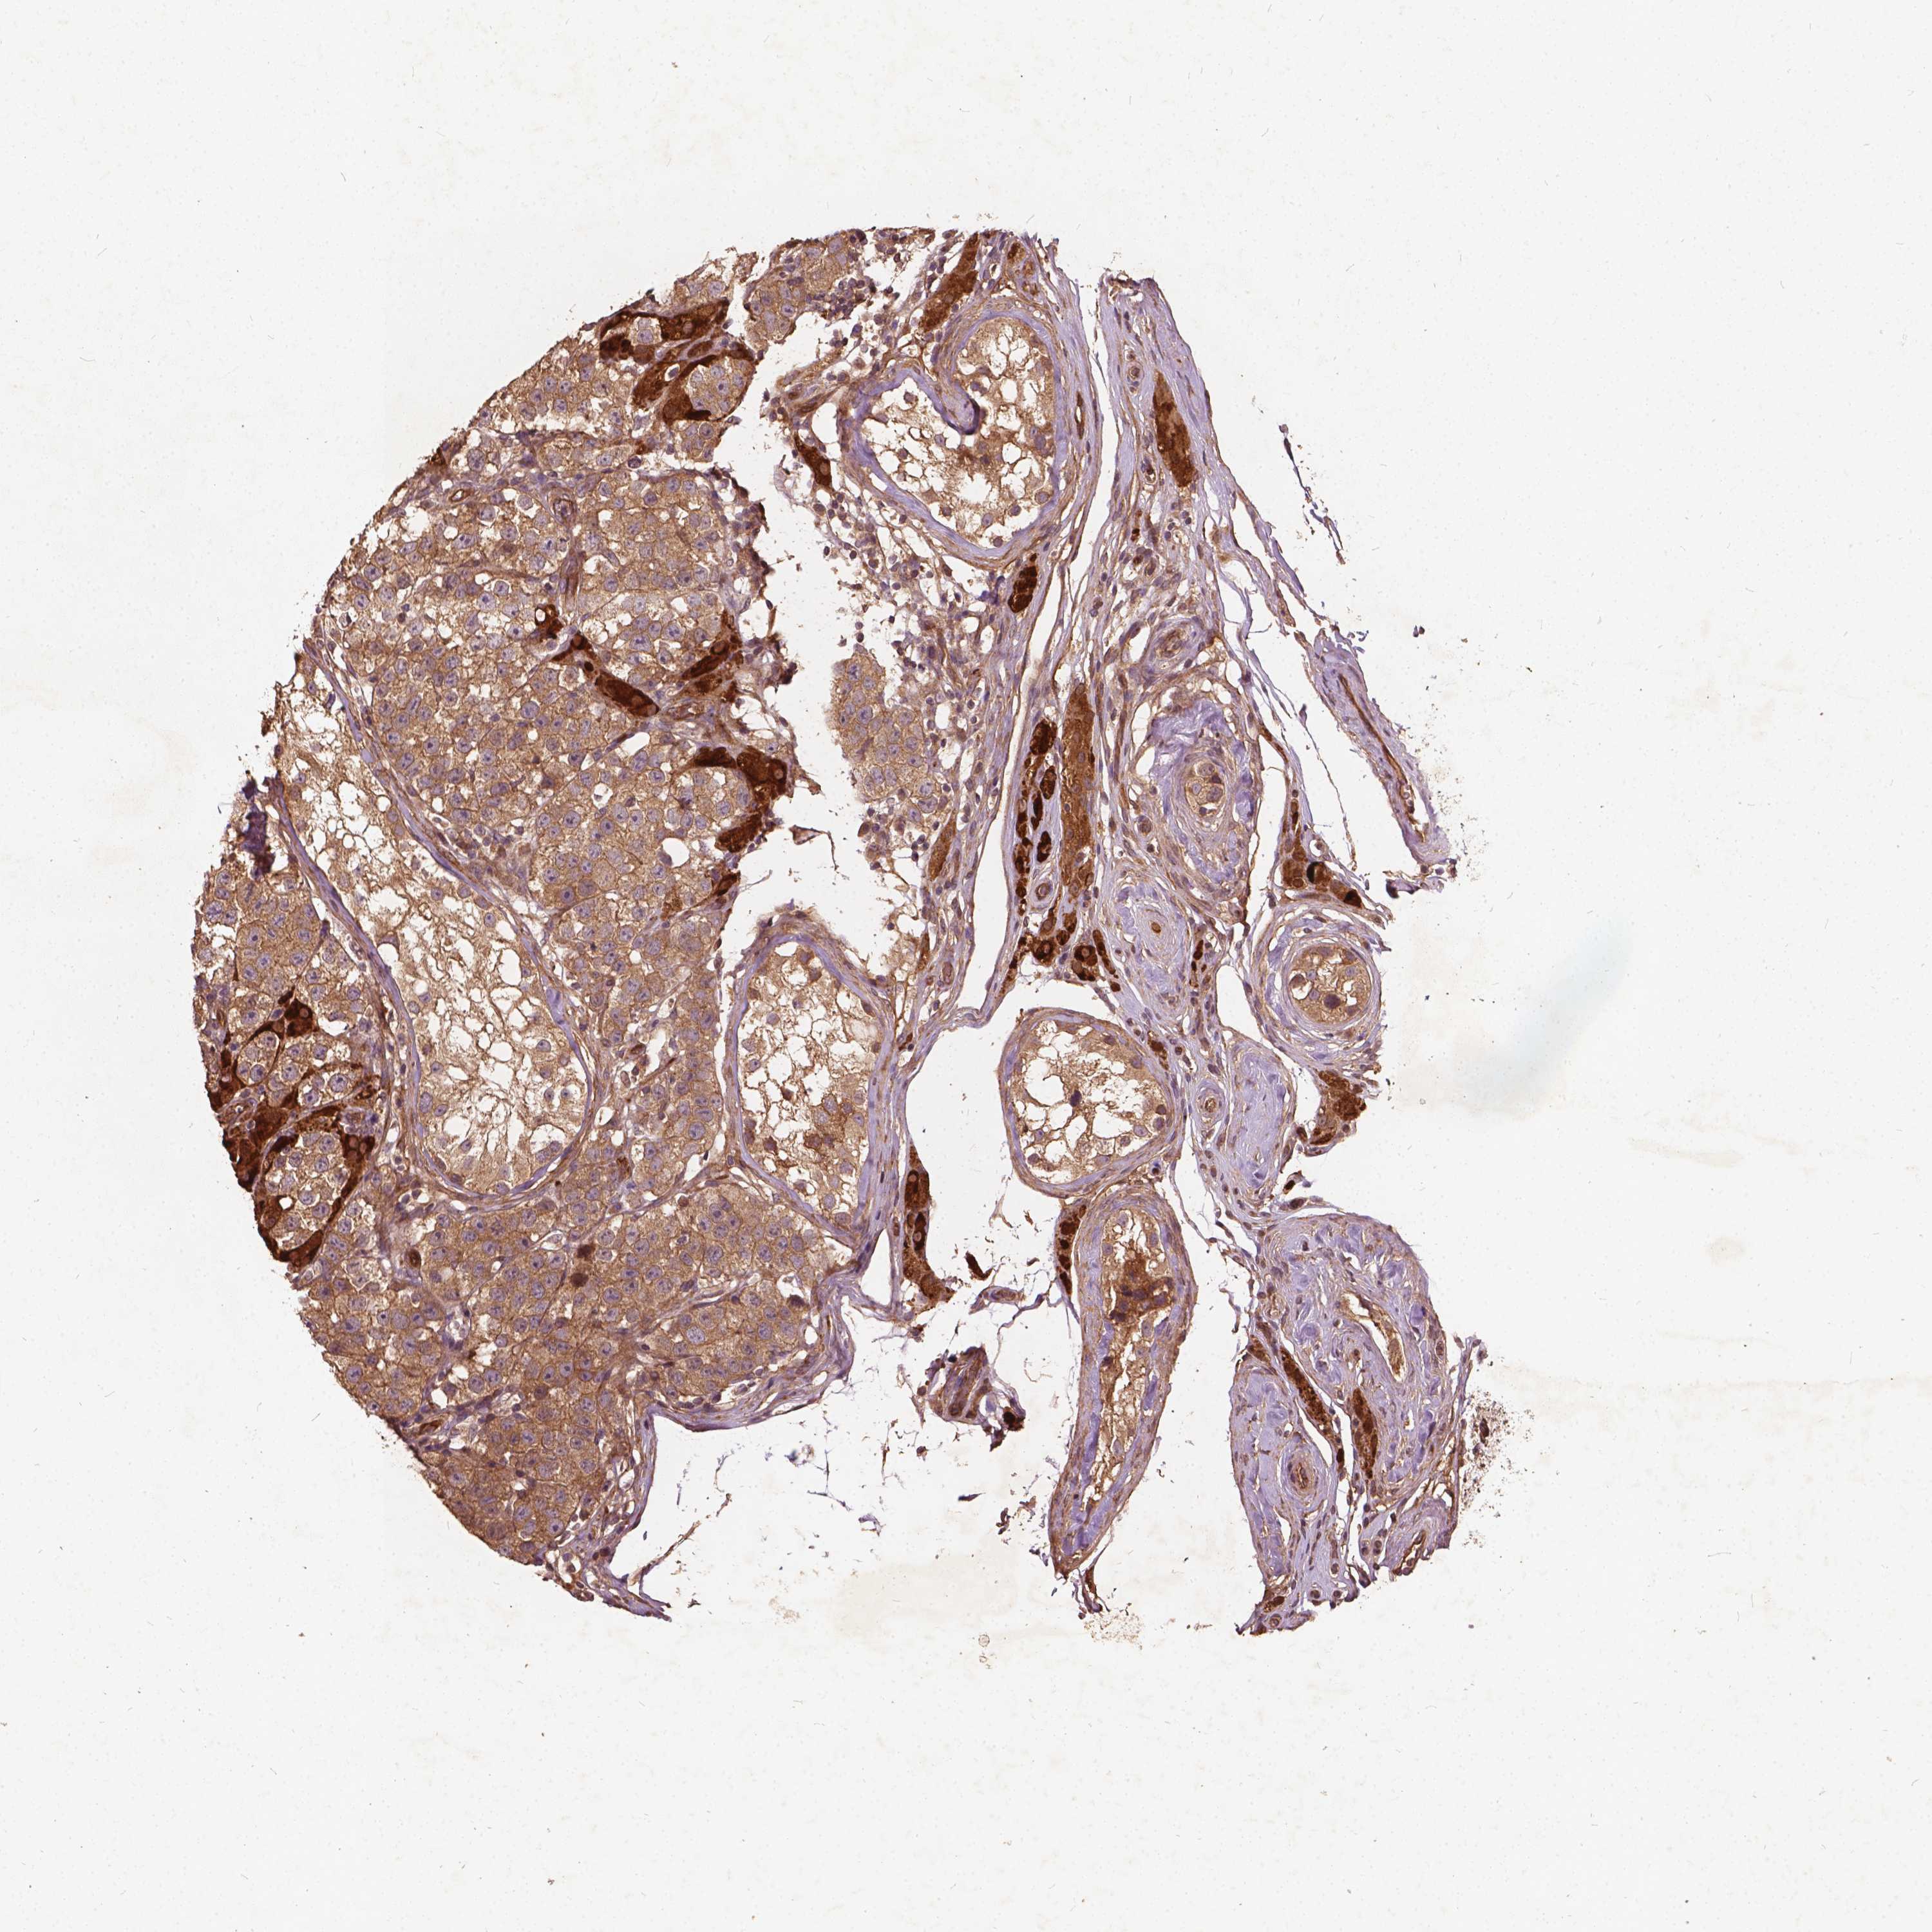

TESTIS CANCER - Protein expressioni

A mouse-over function shows sample information and annotation data. Click on an image to view it in a full screen mode. Samples can be filtered based on level of antibody staining by selecting one or several of the following categories: high, medium, low and not detected. The assay and annotation is described here.

Note that samples used for immunohistochemistry by the Human Protein Atlas do not correspond to samples in the TCGA dataset.

Antibody stainingi

Antibody staining in the annotated cell types in the current human tissue is reported as not detected, low, medium, or high, based on conventional immunohistochemistry profiling in selected tissues. This score is based on the combination of the staining intensity and fraction of stained cells.

Each image is clickable and will lead to virtual microscopy that enables deeper exploration of all samples and also displays staining intensity scores, fraction scores and subcellular localization as well as patient and tissue information for each sample.

Antibody HPA065482

Antibody HPA069096

Staining

High

Medium

Low

Not detected

Intensity

Strong

Moderate

Weak

Negative

Quantity

>75%

75%-25%

<25%

None

Location

Nuclear

Cytoplasmic/membranous

Cytoplasmic/membranous,nuclear

Seminoma, NOS

Carcinoma, Embryonal, NOS

Teratoma, malignant, NOS